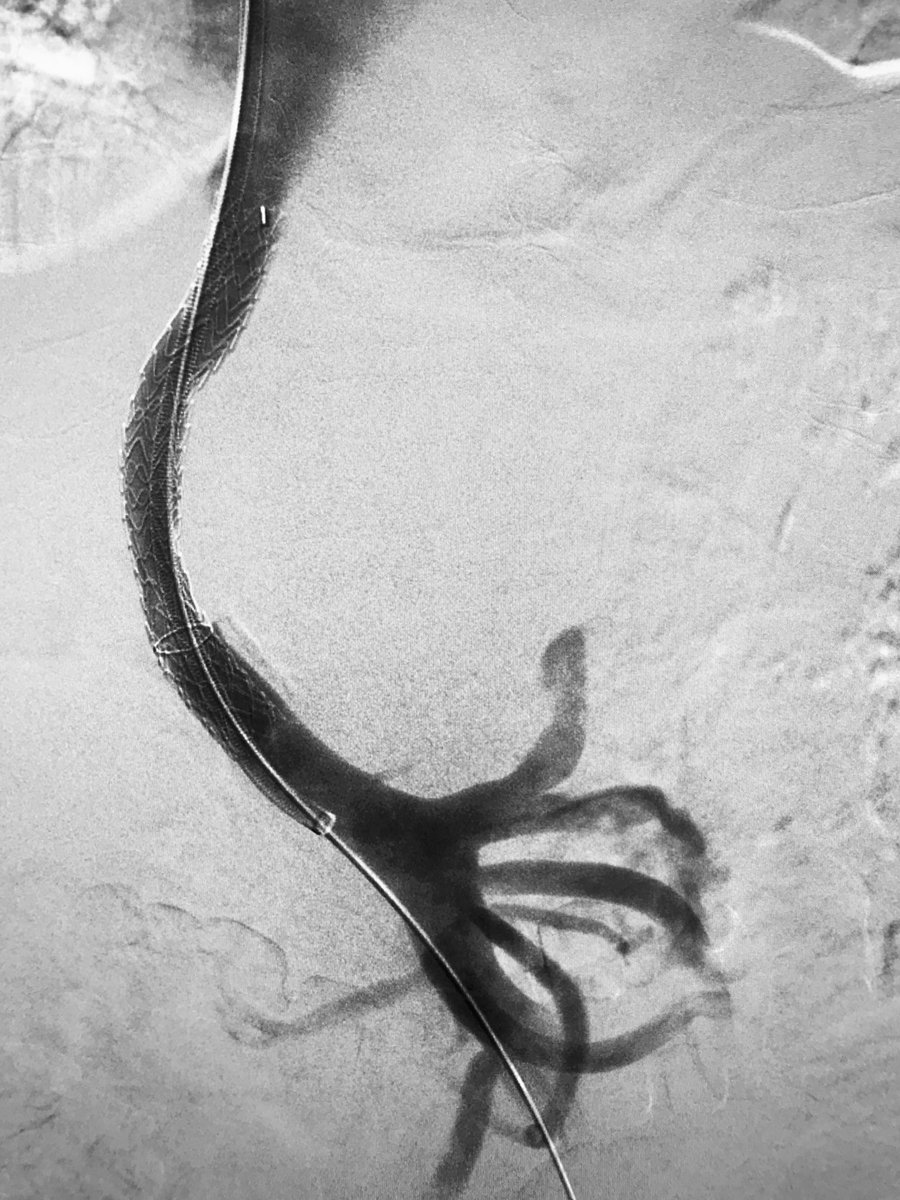

Large floating IVC thrombus extending into both iliacs. Suprarenal #filterIN. Boston Scientific Angiojet, #singlesession lysis/thrombectomy. #filterOUT before she left the room. Thanks to Kris Schramm for his help! Kush Desai @rkryu #IRad

LIVE Mount Sinai IR Transradial Transplant Hepatic Artery Stenosis | FFR 0.49 | IVUS for vessel caliber measurement | Not a lot of running room til the left takeoff! | Herculink 5.5 x 12 mm with resolution of gradient #ThinkRadial #Transplant Abbott @sirrfs American Society of Transplantation (AST)